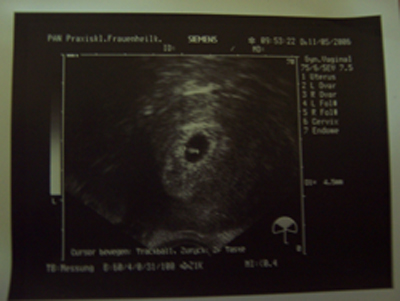

Es ist alles ok. Das Herzchen schlägt und unser Krümelchen ist 4,5mm groß :D Bin voll happy.

Dateianhänge

2. US 2.jpg

2.US am 11.05 das Herzchen schlägt :D